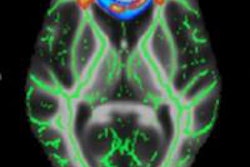

Diffusion-tensor images were acquired before and after the season on a 3-tesla MRI scanner (Siemens Healthcare). DTI-MRI is used to measure the movement of water molecules along millions of nerve fibers, called axons, which make up the brain's white matter. The measurement is known as fractional anisotropy.

In healthy white matter, the direction of water movement is fairly uniform and results in high fractional anisotropy values. When water movement is more random, fractional anisotropy measurements decrease, suggesting that there might be some microstructural abnormalities.

In their analysis of the images, the researchers found that both the heavy-hitter and light-hitter groups demonstrated increases in fractional anisotropy before and after the season, likely due to the effects of adolescent brain development.

However, the heavy-hitting football players showed statistically significant decreases in fractional anisotropy after the season in specific areas of the brain, including the corpus callosum and deep white-matter tracts. The players did not show any symptoms or signs of clinically diagnosed concussion.